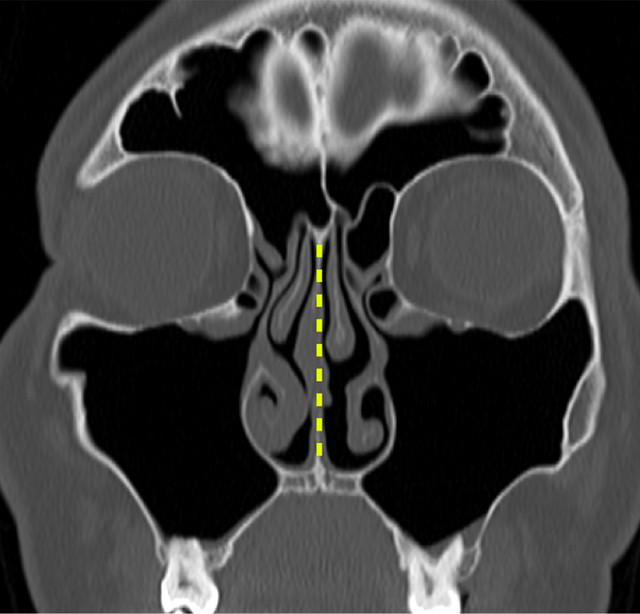

비중격 교정술

코 안쪽의 휘어진 연골이나 뼈를 교정하거나

돌출된 부분을 절제하여 코막힘을 해소하는 수술입니다.

이 수술은 코 안쪽으로 진행되므로 겉으로 보이는 흉터가 없으며,

약물 치료 등 보존적인 방법으로 증상이 개선되지 않을 때 고려됩니다.

수술 전

수술 후

비중격 교정술은 콧구멍 안쪽으로 수술이 이루어져 겉으로 보이는 상처나 흉터가 없으며, 코 본연의 기능을 회복하는 데 중점을 둡니다.

삼성 진 이비인후과에서는 개인의 비중격 만곡 정도와 코 내부 구조에 맞춰 가장 안전하고 효과적인 수술 방법을 적용합니다.